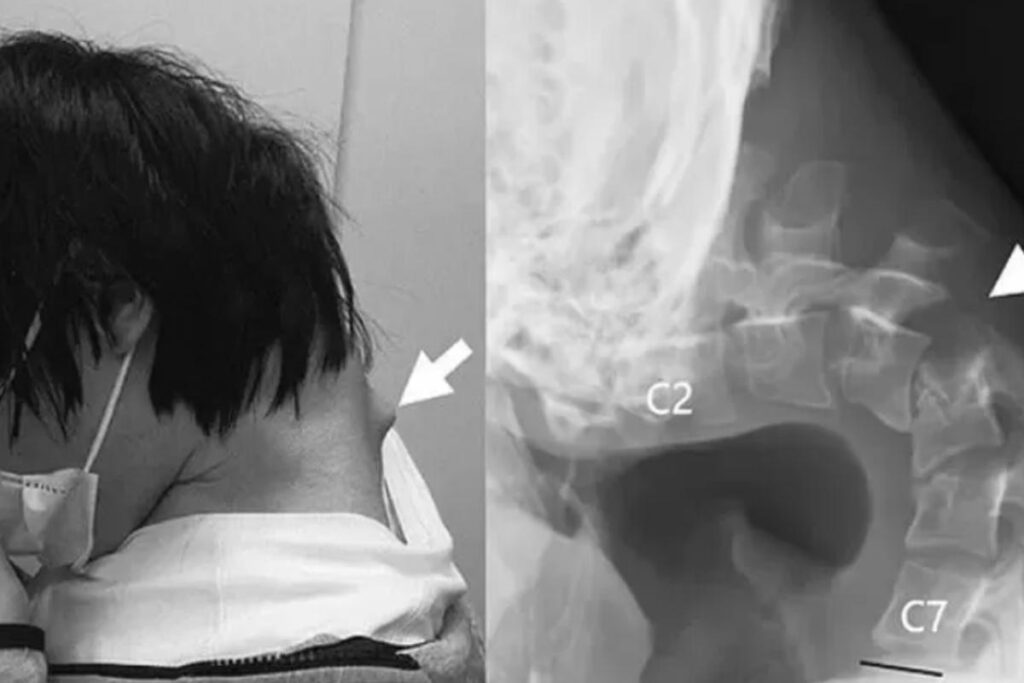

Di recente, in Giappone, sono state rese pubbliche alcune immagine che mostrano gli effetti devastanti della sindrome della testa cadente sul corpo di un ragazzo di 25 anni. Questa rara malattia, che causa la mancanza di forza muscolare, impedisce a chi ne soffre di tenere la testa nella sua naturale posizione. Il paziente, dunque, si ritrova impossibilitato a sollevare la testa, una condizione debilitante spesso preceduta da forti dolori al collo. Nel caso specifico del 25enne giapponese, i medici, pubblicando un rapporto clinico sulla rivista JOS Case Reports, hanno collegato la sua rara condizione all’uso prolungato del telefono.

Nel quadro clinico pubblicato dai medici, emergono alcuni significativi dettagli riguardo al passato del ragazzo. Dopo un’infanzia particolarmente attiva, il ragazzo, nel corso dell’adolescenza, è stato vittima di gravi atti di bullismo, che lo hanno portato a ritirarsi dalla vita sociale e a isolarsi nella sua cameretta. Qui ha trovato conforto nel suo cellulare, che il ragazzo utilizzava per molte ore al giorno giocando ai videogiochi. Per diverse ore nell’arco della giornata, assumeva una particolare postura mantenendo il collo in una posizione di estrema flessione. Nel tempo, a causa di quella postura errata e prolungata, le sue vertebre cervicali si sono gravemente distorte e dislocate.

Il ragazzo ha iniziato così ad accusare fortissimi dolori al collo, oltre alla difficoltà di deglutire correttamente, una condizione che lo ha portato anche a perdere sensibilmente peso. Nel tempo, il suo collo era diventato così debole che il ragazzo non riusciva più a sollevare la testa. Dopo un primo consulto medico, si è cercato di alleviare il suo dolore attraverso l’utilizzo di un collare ortopedico. La cura, rivelatasi inutile, è stata sospesa dopo poche settimane, a causa del dolore che il ragazzo continuava a lamentare. Alla fine, si è deciso di percorrere la via dell’operazione chirurgica, sviluppatasi in più fasi. I medici hanno prima rimosso piccoli segmenti delle vertebre compromesse e parte del tessuto cicatriziale. Poi hanno impiantato una struttura di viti e barre metalliche nelle ossa cervicali per correggere la postura del ragazzo.

Alla fine, il complicato intervento ha dato i suoi frutti e diversi mesi dopo l’operazione il paziente era di nuovo in grado di mantenere la testa sollevata attraverso una postura corretta. Con la pubblicazione di questo studio dettagliato, i medici hanno cercato di sottolineare quali possono essere le possibili e gravi conseguenze di una postura scorretta prolungata quando si è eccessivamente chinati sullo schermo del telefono, rivelando quanto i casi relativi a questo fenomeno siano in costante aumento.